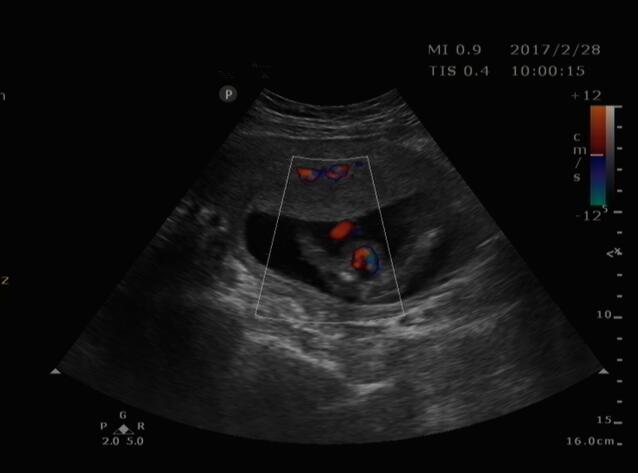

近日,家住商河怀孕4个月的某女士,来我院超声科就诊。接诊大夫为其认真仔细检查,发现该患儿双顶径小于孕周,形态不规则,呈“柠檬头征”,后发现顶枕部一囊性包块,其内含部分脑组织结构,膨出于颅骨外,胎儿其它肢体结构未发现异常。经沟通,此前该女士未做过其它任何检查。随后,该女士在我院办理住院,引产后已证实超声诊断。再进一步了解中得知已孕育两个孩子,其一患有脑积水。

1、头颅中线位置颅骨壁缺损。

2、缺损处突出一包块,脑膜膨出突出内容物为脑膜,膨出物为囊性肿物,脑膜脑膨出突出内容物为脑膜几脑组织,膨出物为实性回声。

3、大量脑组织膨出时颅骨光环缩小或不规则,双顶径可能偏小。